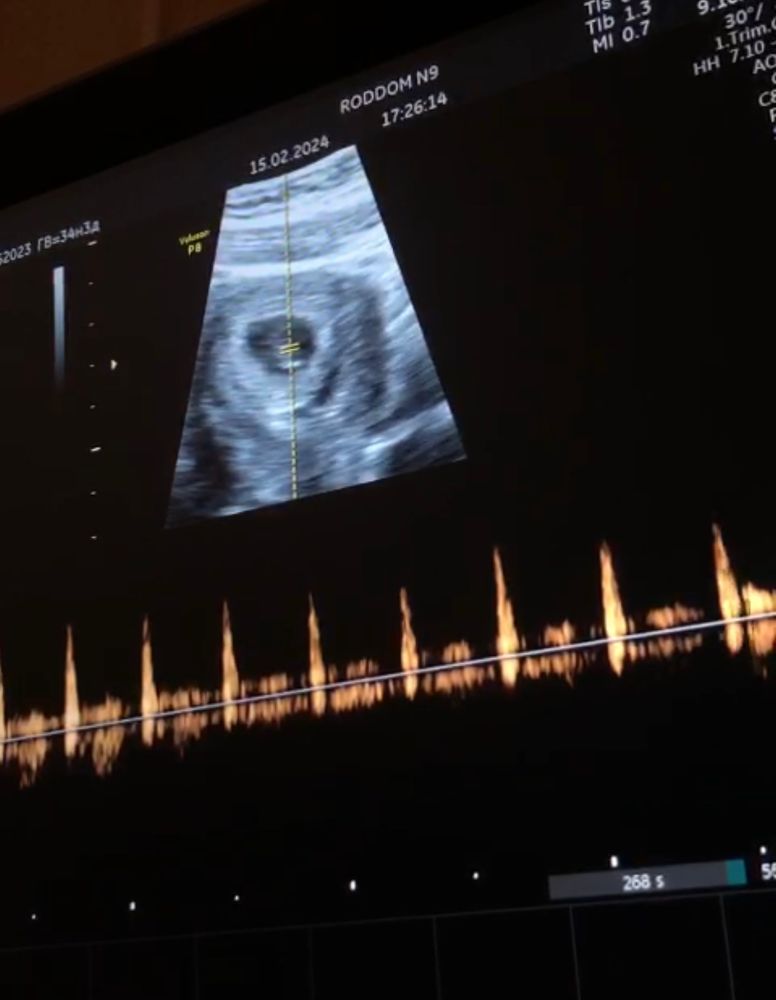

Бог услышал молитвы, на узи наконец-то сб+

Анни, Изображениевот она, наша анэмбриония) а сколько слез было вылито из-за волнения! Верьте в лучшее, ваше от вас не уйдёт!